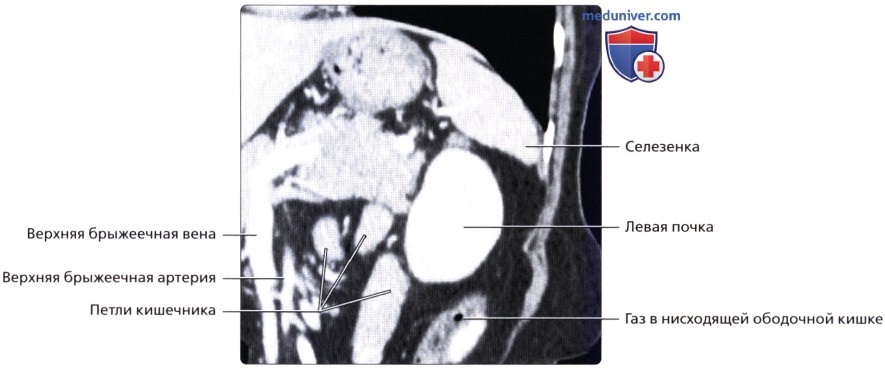

Несмотря на то что почки располагаются в забрюшинном пространстве, от кишечника их отделяет лишь пристеночный листок брюшины. Такая близость органов по отношению друг к другу может затруднять диагностику в случае значительного скопления газов в ЖКТ.

а) Анатомия почек:

б) Лучевая анатомия почки:

1. Обзор:

• Забрюшинные структуры бобовидной формы с четким контуром, смещающиеся при дыхании

• Левая почка:

о Ее труднее визуализировать из-за газа в тонкой кишке и в селезеночном изгибе ободочной кишки